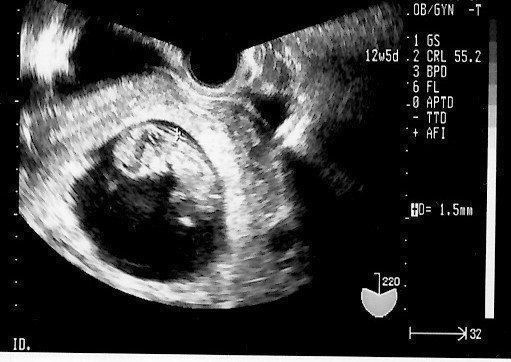

エコー画像で赤ちゃんを感じ、不安も乗り越えた【初めてのマタニティライフ】 -

おなかの中にいる時からそっくり! 今見ても笑っちゃう【第1子エコー写真】 -